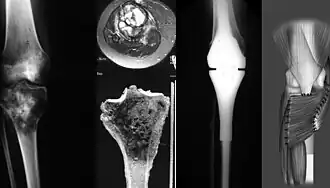

Le diagnostic de cette pathologie est suggéré à l’aide de techniques d’imageries comme la radiographie, l’IRM, la scintigraphie osseuse, la tomodensitométrie, puis confirmé par biopsie[11],[12].

Le traitement comprend le plus souvent [13] :

- un retrait de la zone tumorale par chirurgie, voire une amputation du membre concerné, avec possible pose de prothèse remplaçant l'os. Il peut aussi être envisagé de faire une reconstruction par lambeau libre à la suite de l’exérèse ou dans le même temps opératoire[14];

- une chimiothérapie combinant différents médicaments, généralement pré-opératoire et postopératoire, alors respectivement nommée néo-adjuvante ou adjuvante.